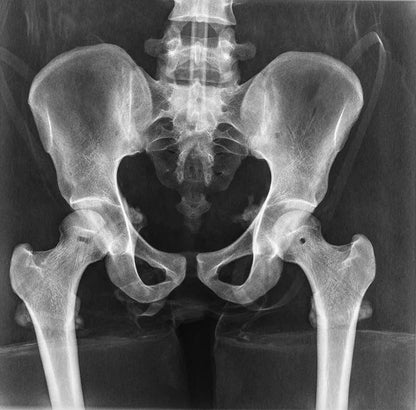

The whole-body X-ray phantom serves for practical training in projection radiography as well as in positioning and positioning techniques. It enables the production of realistic X-ray images under training conditions and depicts anatomical structures in their natural size.

The phantom contains a natural human skeleton. Additionally, the outlines of the larynx, lungs, heart, and kidneys are integrated, appearing as shadows on the X-ray images. This allows for the creation of images that accurately reflect the conditions found in patients. The use of a real skeleton enables the identification of bony landmarks that are not visible in plastic models.

The joints are mounted with full mobility, allowing positioning in common radiological standard positions, including special positions such as the frog position and pronation and supination of the forearm. The arms can be raised, so the phantom can also be used for bone examinations in CT scans. Particular attention was paid during assembly to the realistic representation of the joint spaces.

Each phantom is a handcrafted, unique piece. Variations in size, design, and appearance are possible. Depending on the model, pathological findings may be present. The revised design was developed in collaboration with a German training institution for medical-technical radiology assistants and meets the requirements of modern training concepts.